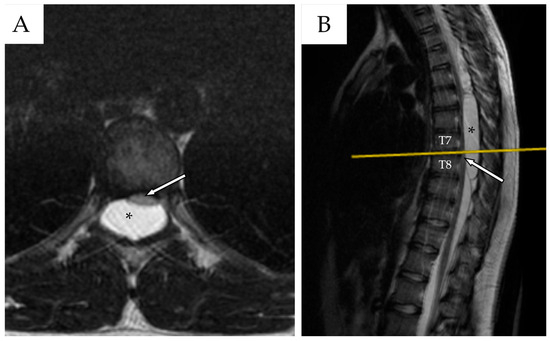

Whole-spine contrast-enhanced Magnetic Resonance Imaging (ceMRI) demonstrated a posterior, extradural intraspinal lesion extending from T2 to T8, causing significant compression of the dural sac and spinal cord (Figure 1). The lesion was formed by two components: a cranial one (T2–T4) and a larger caudal one (T5–T8). The area of maximal spinal cord compression was identified at T7–T8, where subtle intramedullary T2 hyperintensity was observed, suggestive of early spinal cord changes consistent with possible myelopathy (Figure 2). The lesion appeared hyperintense on T2-weighted images, isointense with CSF, and showed no contrast enhancement—findings consistent with a spinal arachnoid cyst.

Figure 2. (A) Thoracic spine ceMRI, axial section, TSE T2-WI. The section is taken at the highest point of spinal cord compression (T7–T8), with early signs of radiological myelopathy (white arrow with black outlines). The spinal cord is dislocated anteriorly against the vertebral posterior wall. The SAC is marked with a black asterisk. (B) The yellow line indicates the level at which the axial section in (A) was obtained.